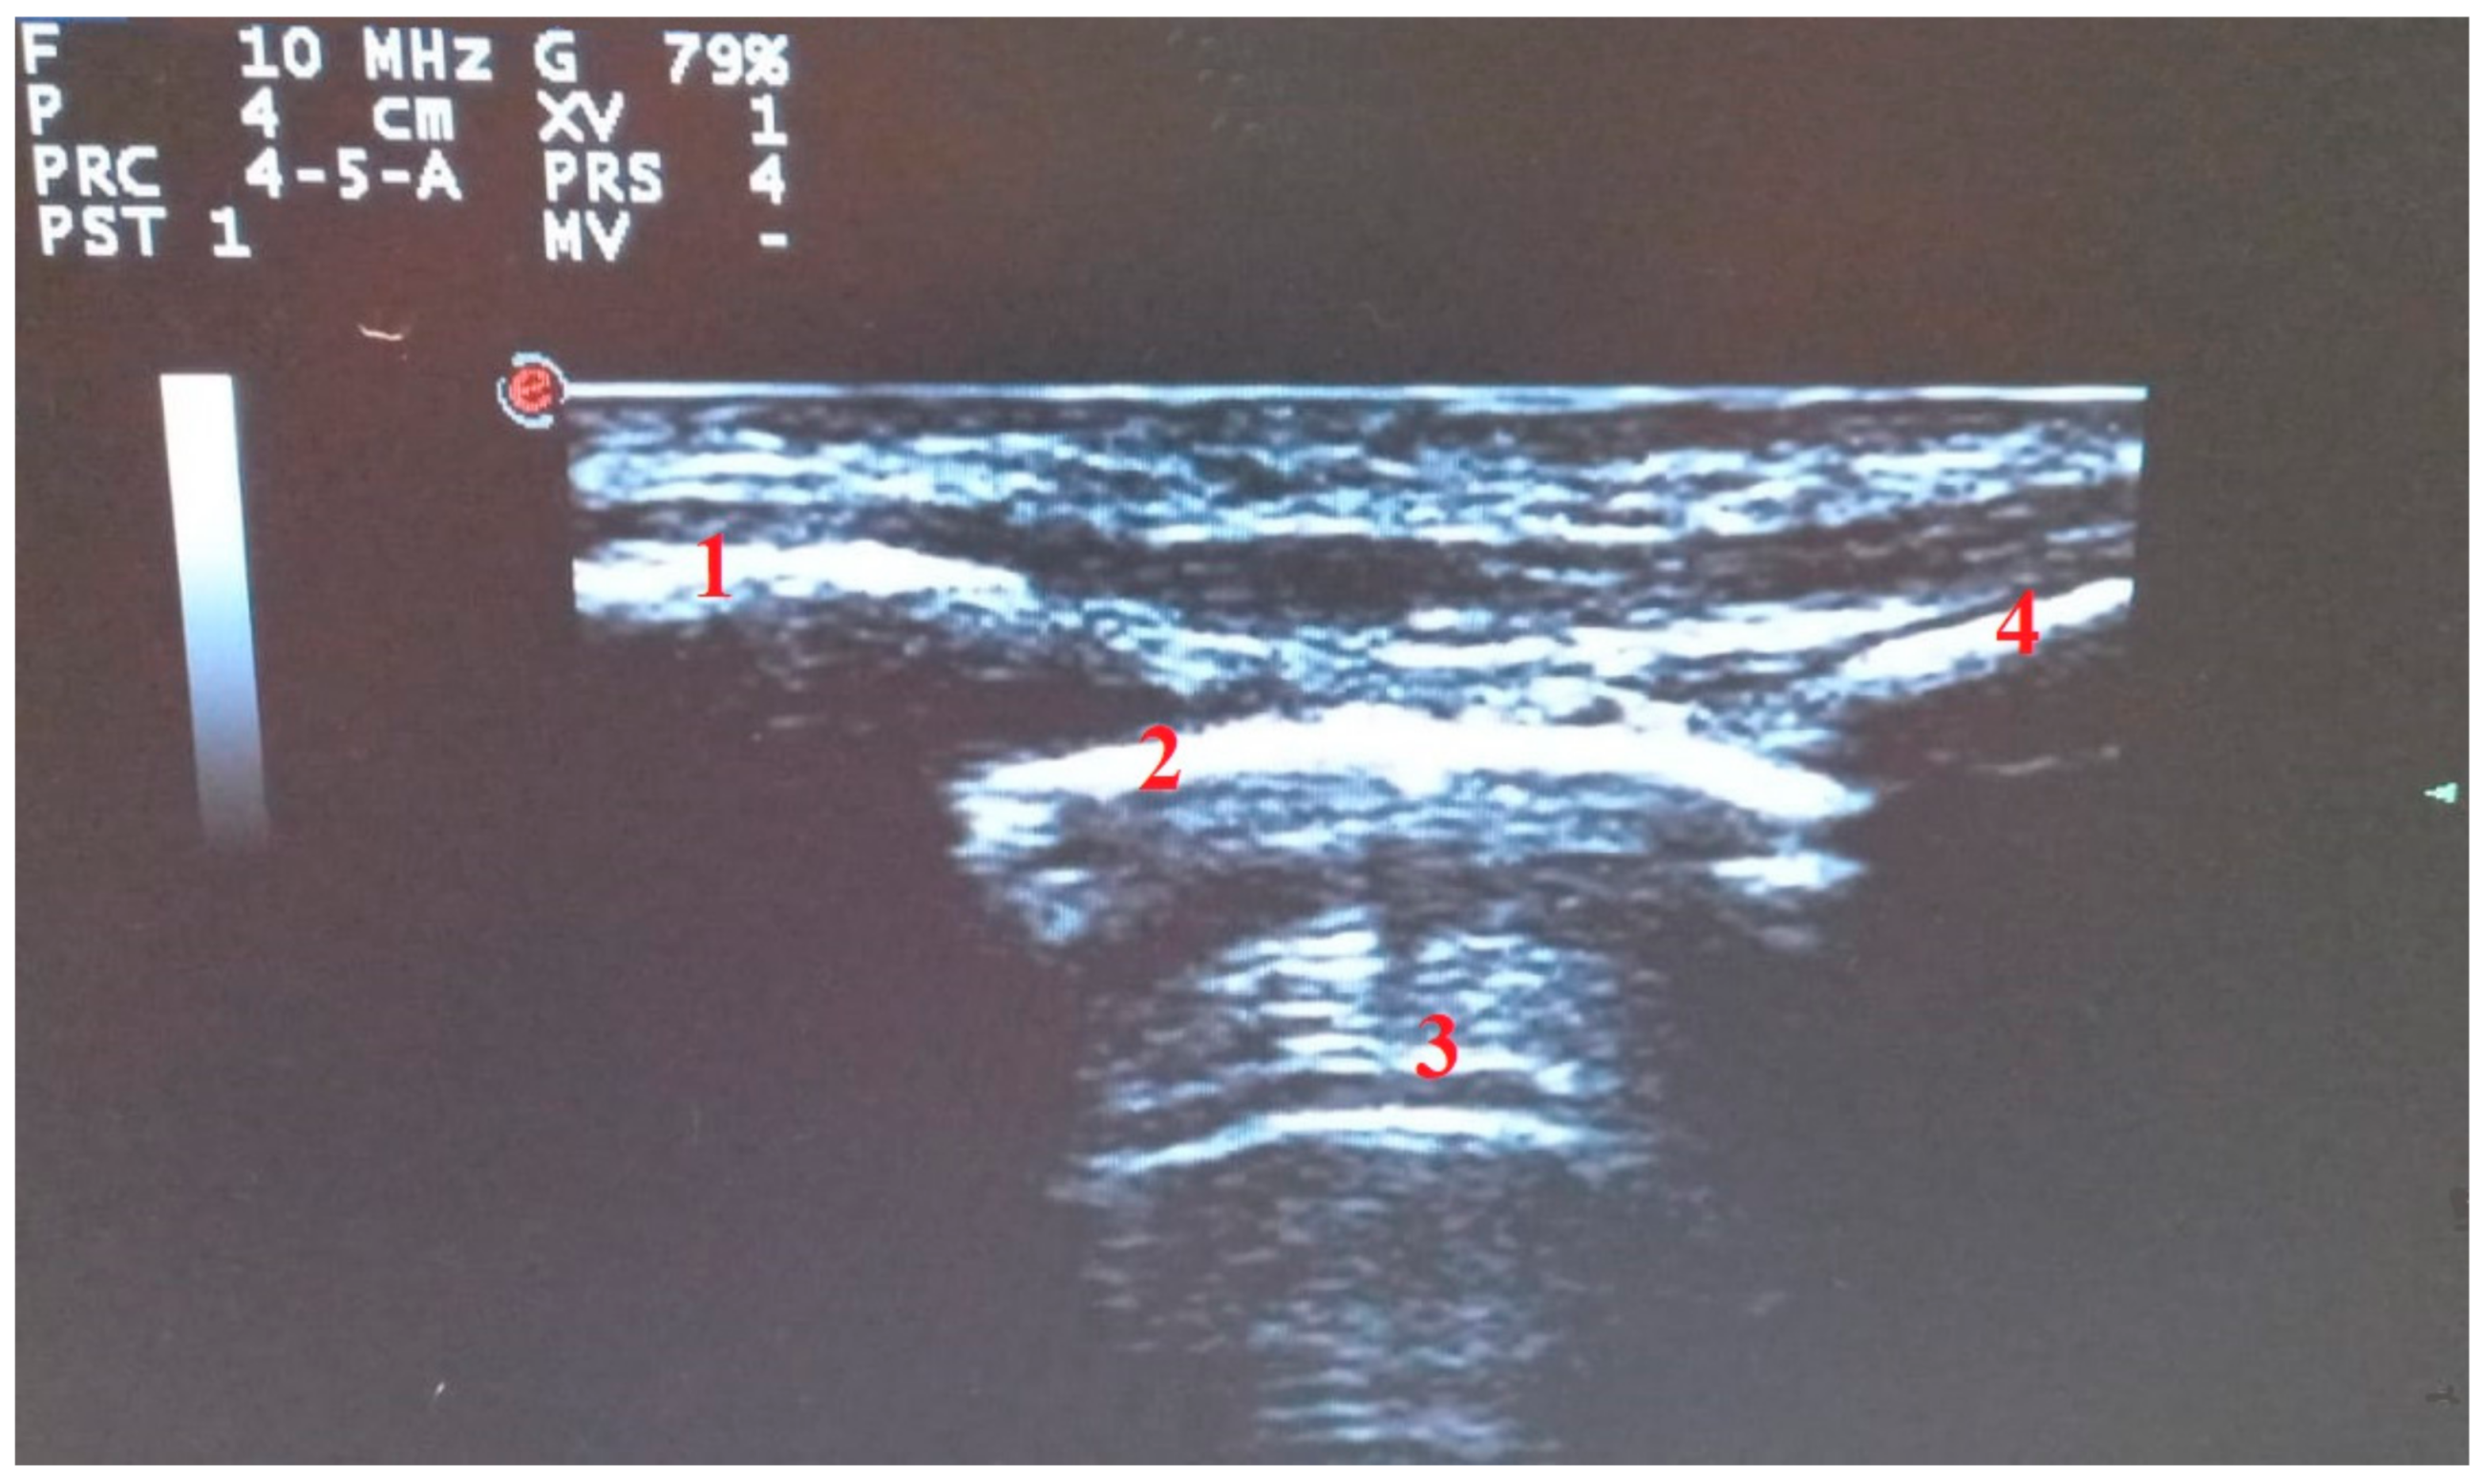

3. Lung Ultrasound in COVID-19 Pneumonia: Findings